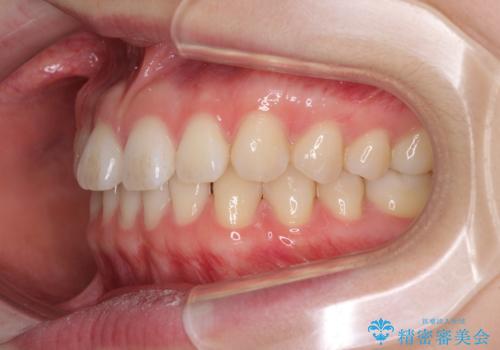

インビザラインによるすきっ歯の改善

- 上の前歯の隙間を気にして来院された患者様です。

インビザラインにより、隙間を閉じながら、隙間の原因であるディープバイトを改善していくこととしました。

下顎の歯列が強く上顎に咬みこむことで隙間ができてしまうため、マウスピースの保定装置では後戻りのリスクが高くなってしまいます。

そのため、上下ともに前歯の裏側を細いワイヤーで固定し、その上から保定装置のマウスピースを使用していただくこととしました。